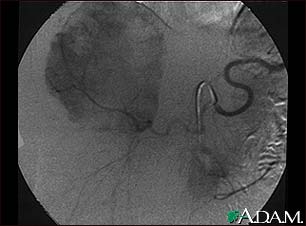

Hemangioma - angiogram

This angiogram (an X-ray taken after dye has been injected into the blood stream) shows a mass of blood vessels (hemangioma) in the liver.